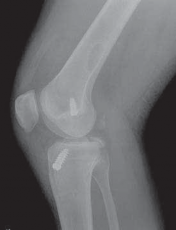

8. Radiographs of the knee should be performed following an acute injury to assess for a fracture. An avulsion of the tibial insertion of the PCL may be identified on a lateral radiograph (

FIG 1A

).

FIG 1 • A. Avulsion fracture of the tibial insertion of the posterior cruciate ligament (PCL). B. Posterior subluxation of the

tibia in a case of chonic PCL deficiency.

1. In the chronic setting, radiographs may identify posterior tibial subluxation (

FIG 1B

) or medial and patellofemoral compartmental arthrosis.